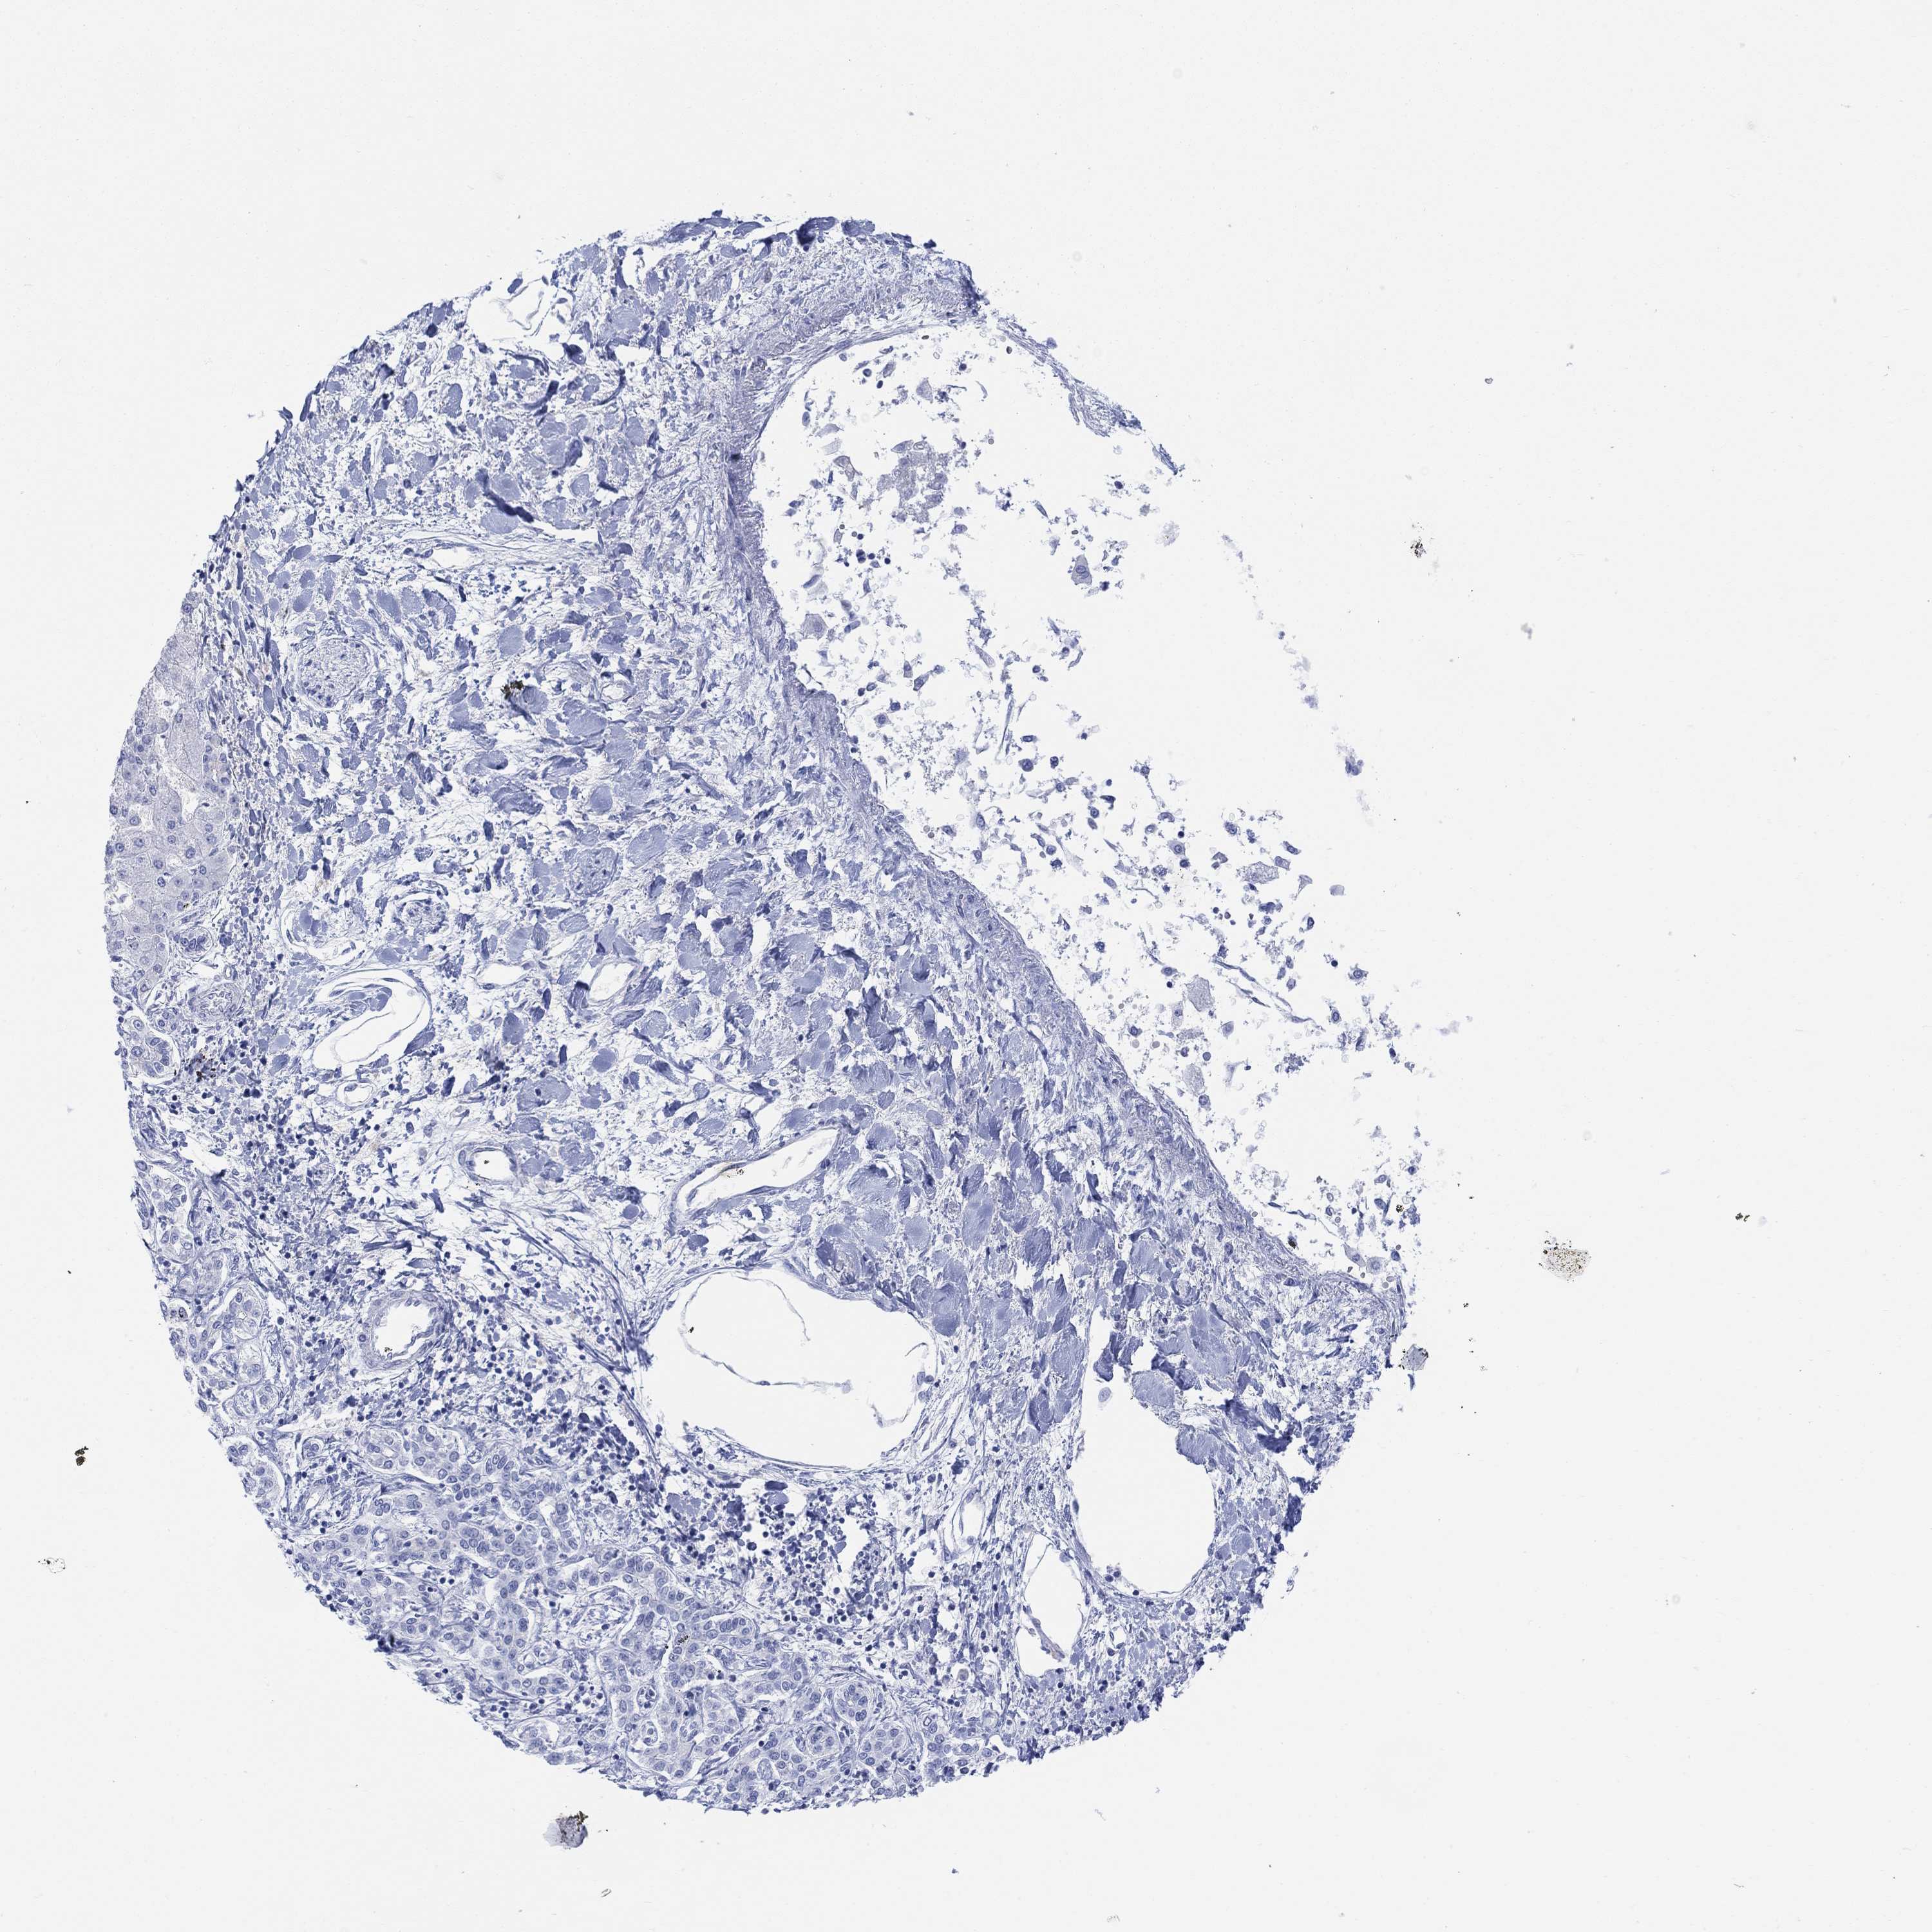

LIVER CANCER - Protein expressioni

A mouse-over function shows sample information and annotation data. Click on an image to view it in a full screen mode. Samples can be filtered based on level of antibody staining by selecting one or several of the following categories: high, medium, low and not detected. The assay and annotation is described here.

Note that samples used for immunohistochemistry by the Human Protein Atlas do not correspond to samples in the TCGA dataset.

Antibody stainingi

Antibody staining in the annotated cell types in the current human tissue is reported as not detected, low, medium, or high, based on conventional immunohistochemistry profiling in selected tissues. This score is based on the combination of the staining intensity and fraction of stained cells.

Each image is clickable and will lead to virtual microscopy that enables deeper exploration of all samples and also displays staining intensity scores, fraction scores and subcellular localization as well as patient and tissue information for each sample.

Antibody HPA046272

Staining

High

Medium

Low

Not detected

Intensity

Strong

Moderate

Weak

Negative

Quantity

>75%

75%-25%

<25%

None

Location

Nuclear

Cytoplasmic/membranous

Cytoplasmic/membranous,nuclear

Carcinoma, Hepatocellular, NOS

Cholangiocarcinoma